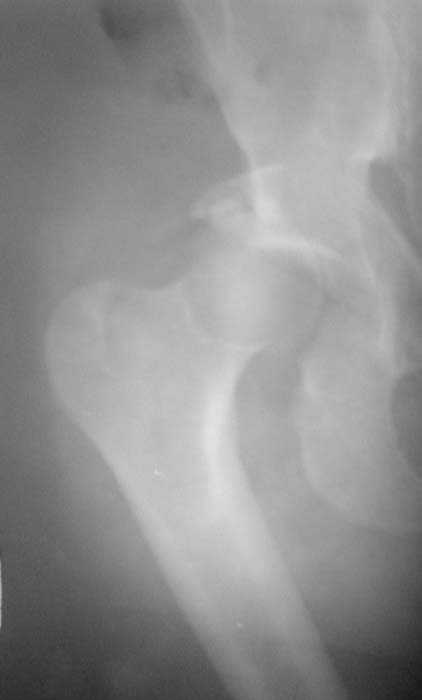

Уважаемые коллеги!Мужчина, 40 лет. Травма несколько месяцев назад. Получил закрытый вывих правого тазобедренного сустава и перелом вертлужной впадины (сним.1).Лечился скелетным вытяжением. Сейчас (сним.2) жалобы на боли, ограничение движений. Вопрос: тактика лечения (эндопротезирование и/или восстановительная операция, иное)?С уважением,А.В.Владзимирский

Вывих, похоже, вообще не был устранен. Или из-за дефекта заднего края сразу рецидивировал.

Для уточнения величины дефекта задней стенки и состояния головки необходима КТ. Если МРТ доступна, то и ее.

Если головка живая, прошло менее 2 мес., то мы бы наложили аппарат, стянули бедро дистально за неделю, потом открыто выполнили бы вправление с реконструкцией заднего края, скорее всего с аутопластикой, и фиксировали мостовидной пластиной (чтобы не мешало в дальнейшем эндопротезу).

Если срок больше, головка плохая, и дефект незначительный, то сразу эндопротезирование. Если значительный дефект и будут сложности, то

предусмотреть усложнение операции эндопротезирования из-за той или иной реконструкции впадины (аутопластика, остеосинтез края, укрепляющее кольцо).